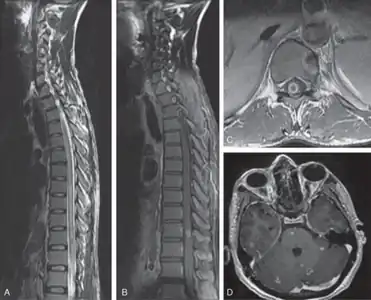

Myeloradiculopathy in tuberculous meningitis[16]-a) Long segment myelitis b,c) intramedullary tuberculoma at D10 level d)multiple tuberculoma involving cerebrum, cerebellum, and brainstem -